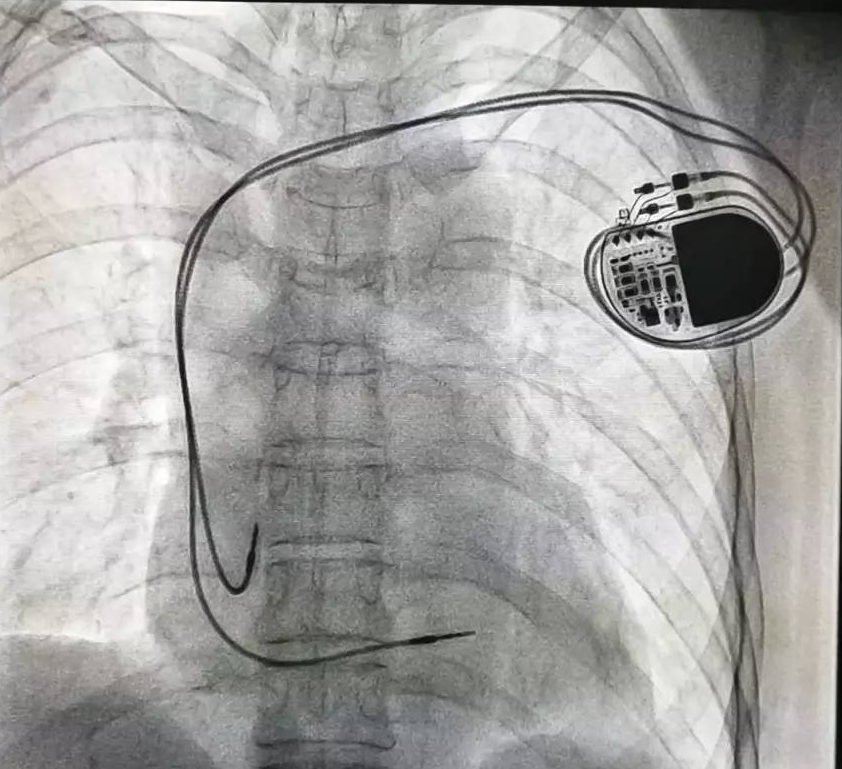

全球唯一!無線雙腔起搏器首次植入

來源:器械之家,未經(jīng)授權(quán)不得以任何形式轉(zhuǎn)載,且24小時后方可轉(zhuǎn)載。2022年2月7日雅培宣布,其在研型Aveir?雙腔無引線起搏器完成了全球首例患者植入,這也是全世界第一個雙腔無線起搏器。Aveir?DR雙腔起搏器提供右心房和心臟右心室的同步、逐次跳起搏,近80%接受起搏器治療的患者需要雙腔選擇,A